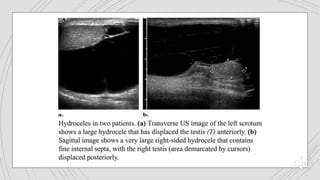

SCROTALTRAUMA

 Ultrasound is the imaging technique of choice